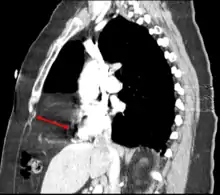

Morgagni hernia

This rare anterior defect of the diaphragm is variably referred to as a Morgagni, retrosternal, or parasternal hernia. Accounting for approximately 2% of all CDH cases, it is characterized by herniation through the foramina of Morgagni which are located immediately adjacent and posterior to the xiphoid process of the sternum.[4]